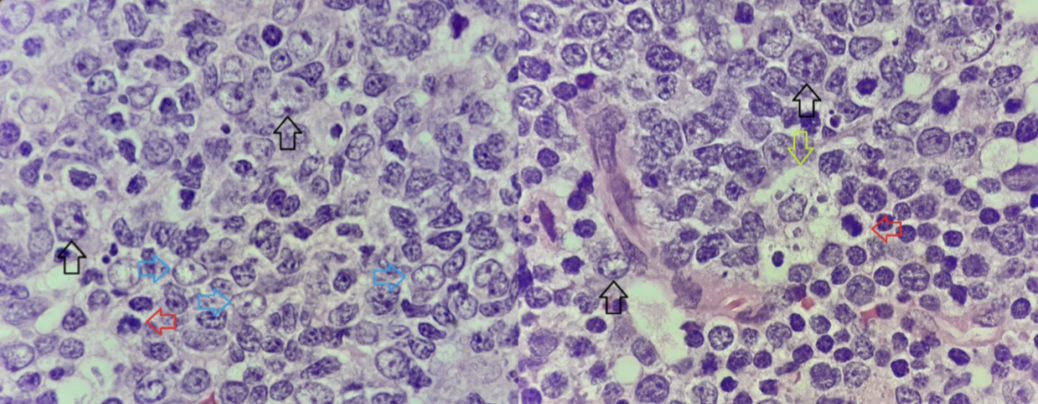

Vad är germinalcentrats histologi?

den består av olika zoner:

Dark zone: Mer centeroblaster. Lite mörkare.

Light zone: Mer centerocyter, FDC och makrofager. Ljusare.

Mantelzon: Små B-lymfocyter med väldigt mörk kärna och sparsam cytoplasma.

Vilka celler finns i GC?

Centerocyt: Finns i dark zone. Små mröka celler med lite cytoplasma. De är kantiga.

Centeroblast (svart): Större och blekare celler med 1-3 nukleoler längst cellmembranet.

FDC (blå): Blekt kromatin, EN central nukleol. Cellerna runtomkring har en tillplattad cellkärna.

Tingible body makrofag (grön): Stora och ljusa med flera celler inuti.

Det röda är mitoser.

Vad pekar pilarna på?

Grön: Makrofag.

Blå: FDC.

Röd: Mitoser.

Svart: Centeroblast.